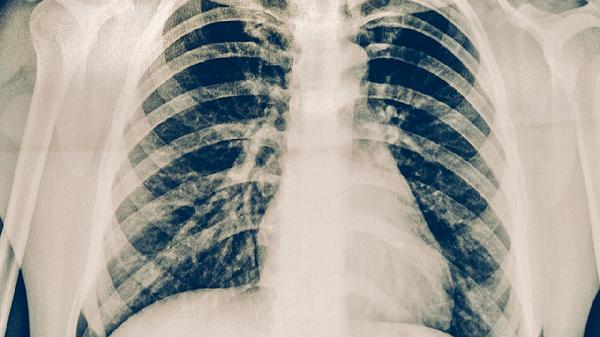

肺心病的诊断需结合病史、体格检查和辅助检查。胸部X线可见肺动脉段突出、右心室增大;心电图显示右心室肥厚特征;超声心动图能直接评估肺动脉压力和右心功能。治疗需兼顾原发肺部疾病和心脏并发症,包括氧疗、支气管扩张剂改善通气,利尿剂减轻心脏负荷,必要时使用血管扩张剂降低肺动脉压力。患者需严格戒烟、避免呼吸道感染,并定期监测心肺功能。